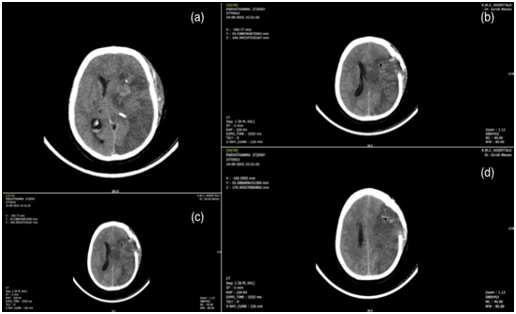

A 65-year-old lady presented with sudden onset of loss of consciousness and right-sided weakness. She was a hypertensive on regular treatment but had no other co-morbidities. On admission, she was intubated and had a GCS of E2M5, stable vitals, and a right hemiplegia. Her CT scan showed a large left putaminal bleed with intraventricular extension and early hydrocephalus (Figure 3) (SICH score 3). After explaining the risks involved, the patient was taken up for an immediate craniotomy and evacuation of the haematoma under GA. The patient was electively ventilated post procedure and started on decongestants. The repeat CT brain done next day showed an evolving infarct over the left ICA territory with oedema (Figure 4) elevating the bone flap and complete effacement of the basal cisterns. She was then immediately taken up for an emergency decompressive craniectomy. Post procedure she was sedated and electively ventilated with decongestants. The post op scan showed a large patchy ICA infarct on the left side with oedema and trans calvarial herniation of the brain through the decompressive craniectomy site. Thereafter, she had a stormy course and was discharged nearly two weeks after the surgery in a vegetative state.

Figure 3 Preoperative axial CT Scans showing a large left putaminal bleed with intraventricular extension and early hydrocephalus (a to d).